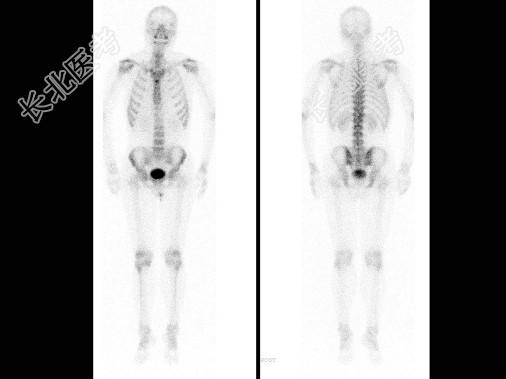

多项选择题男,肝癌术后1年, 诉腰背痛5个月,行全身骨显像如图, 碱性磷酸酶明显增高,可能的诊断为 ( )

A、大致正常的骨影像

B、肝癌骨转移“冷区”较常见

C、胸12有溶骨性病变

D、胸12骨转移瘤

E、胸12“冷区”